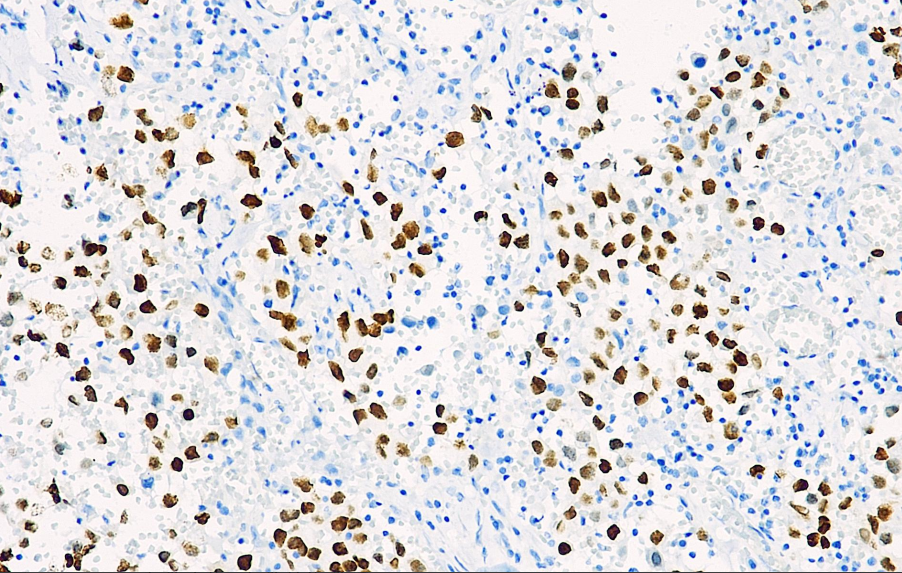

Positive control: Spermatogonial tumor

SALL4 is a newly discovered zinc finger transcription factor that maintains the totipotency of embryonic stem cells by regulating Oct4. SALL4 is a novel, sensitive, and highly specific marker for metastatic germ cell tumors and can be used to study and detect metastatic yolk sac tumors. Its positive expression rate is 100% in seminoma, 100% in dysgerminoma, 100% in embryonal carcinoma, 100% in yolk sac tumor, 50% in teratoma, and 71% in choriocarcinoma.

SALL4 antibody reagents can specifically bind to the SALL4 molecular antigen. Immunohistochemistry kits containing SALL4 antibody reagents are suitable for the auxiliary diagnosis of germ cell tumors (such as seminoma and yolk sac tumor) and certain acute leukemias (such as AML).